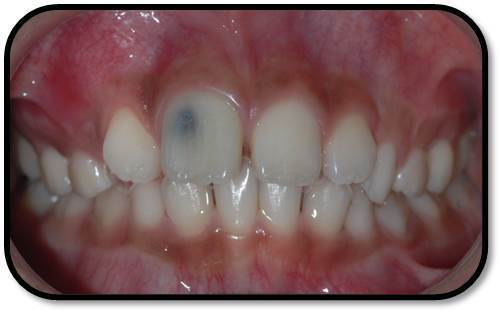

检查: 右上1牙冠略宽大,舌侧见粗大的畸形舌尖,叩痛(++),松Ⅰ°,唇侧牙龈红肿前庭沟膨隆扪痛,挤压唇侧龈缘溢脓,冷热测无反应,右侧上下1侧方颌,正中颌颌创伤。 X线:右上1发育7-8期,根管平行状,根尖孔宽大,约5-6mm宽,根尖周低密度影。髓腔根管宽大内见倒置牙影像,倒置牙可见髓腔。 余牙未见异常 6均已萌出建颌

随访复查: 治疗完成后1个月复查:右上1临床检查无阳性体征,叩痛(—),冷测无反应,无松动,牙龈无红肿,充填物完好,牙冠略有变色, X线检查:牙根根继续发育,可见钙化影像形成,如图示 治疗完成后7个月复查:临床检查无阳性体征,充填物完好,牙冠变色局部发黑,叩痛(—),冷测无反应,无松动,牙龈无红肿,临床及 X线检查:牙根继续发育,如图示 治疗完成后17个月复查:临床检查无阳性体征,充填物完好,牙冠变色局部发黑,叩痛(—),冷测无反应,无松动,牙龈无红肿。X线:牙根继续发育,根尖孔已近闭合。如图 讨论: 1、牙内陷(Dens invaginatus):是牙冠在生物学矿化开始前的内陷引起的一种罕见牙齿畸形。文献报道,牙内陷的发生率为0.04-10%不等,好发于上颌侧切牙。尖牙,双尖牙,磨牙,下颌侧切牙也有报道。 2、Oehlers将牙内陷畸形牙分为Ⅰ型和Ⅱ型均为釉质阻射层包绕的细沟状透射影,不同的是Ⅰ型局限于牙冠部分,不超过釉牙骨质界。Ⅱ型超过釉牙骨质界延伸至根管内,但不与牙周膜相通。Ⅲ型表现为囊袋状或细沟状透射影,由釉质阻射层包绕,由牙冠部延伸至根尖区,与牙周膜相通。其中type Ⅱ和type Ⅲ型根管系统极其复杂。内陷部位的釉质和牙本质可能有缺陷或缺失,很可能与牙齿髓腔有交通,这些特点使得该部位易龋坏且易进展影响牙髓 ,而且此类牙牙周组织不连续,易形成深牙周袋 ;畸形舌尖随牙齿萌出妨碍咬合,造成咬合创伤,尖细的畸形舌尖髓角长入,易于磨损或折断,极易发生牙髓炎症或者根尖炎症。由于根管系统复杂,所以治疗极其困难。 3、牙内陷的治疗: a、内陷处易患龋—尽早窝沟封闭或PRR,已龋坏者及时治疗,避免发展为牙髓炎根尖炎。 b、畸形舌尖不妨碍咬合较圆钝者可不做处理 c、干扰咬合和高而尖的舌尖可磨除畸形舌尖选择间接盖髓术、直接盖髓、部分冠髓切断。 d、牙髓已受累根据牙髓感染情况和牙根发育情况选择根管治疗、牙髓再血管化、MTA根尖封闭、根尖诱导成形。 e、内陷程度较重的Oehlers Ⅲ型患牙,因内陷结构与根尖区牙周膜相通, 其内容纳的细菌物质导致根尖周炎发生时, 通过常规根管治疗并不能使病变痊愈,还需根尖切除术加MTA倒充填。 f、拔除患牙。 4、内陷盲袋清理治疗时应注意:a、推荐手用根管锉,不推荐旋转镍钛,因为内陷盲袋内壁覆盖釉质,而非牙本质壁,且盲袋形状不规则,使用旋转镍钛器械容易折断。b、推荐使用超声根管预备(Bishop,2008)。c、推荐2.5%-5.25%次氯酸钠化学预备。